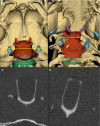

The synchronization of flight mechanics with respiration and echolocation call emission by bats, while economizing these behaviors, presumably puts compressive loads on the cartilaginous rings that hold open the respiratory tract. Previous work has shown that during postnatal development of Artibeus jamaicensis (Phyllostomidae), the onset of adult echolocation call emission rate coincides with calcification of the larynx, and the development of flight coincides with tracheal ring calcification. In the present study, I assessed the level of reinforcement of the respiratory system in 13 bat species representing six families that use stereotypical modes of echolocation (i.e. duty cycle % and intensity). Using computed tomography, the degree of mineralization or ossification of the tracheal rings, cricoid, thyroid and arytenoid cartilages were determined for non-echolocators, tongue clicking, low-duty cycle low-intensity, low-duty cycle high-intensity, and high-duty cycle high-intensity echolocating bats. While all bats had evidence of cervical tracheal ring mineralization, about half the species had evidence of thoracic tracheal ring calcification. Larger bats (Phyllostomus hastatus and Pterpodidae sp.) exhibited more extensive tracheal ring mineralization, suggesting an underlying cause independent of laryngeal echolocation. Within most of the laryngeally echolocating species, the degree of mineralization or ossification of the larynx was dependent on the mode of echolocation system used. Low-duty cycle low-intensity bats had extensively mineralized cricoids, and zero to very minor mineralization of the thyroids and arytenoids. Low-duty cycle high-intensity bats had extensively mineralized cricoids, and patches of thyroid and arytenoid mineralization. The high-duty cycle high-intensity rhinolophids and hipposiderid had extensively ossified cricoids, large patches of ossification on the thyroids, and heavily ossified arytenoids. The high-duty cycle high-intensity echolocator, Pteronotus parnellii, had mineralization patterns and laryngeal morphology very similar to the other low-duty cycle high-intensity mormoopid species, perhaps suggesting relatively recent evolution of high-duty cycle echolocation in P. parnellii compared with the Old World high-duty cycle echolocators (Rhinolophidae and Hipposideridae). All laryngeal echolocators exhibited mineralized or ossified lateral expansions of the cricoid for articulation with the inferior horn of the thyroid, these were most prominent in the high-duty cycle high-intensity rhinolophids and hipposiderid, and least prominent in the low-duty cycle low-intensity echolocators. The non-laryngeal echolocators had extensively ossified cricoid and thyroid cartilages, and no evidence of mineralization/ossification of the arytenoids or lateral expansions of the cricoid. While the non-echolocators had extensive ossification of the larynx, it was inconsistent with that seen in the laryngeal echolocators.